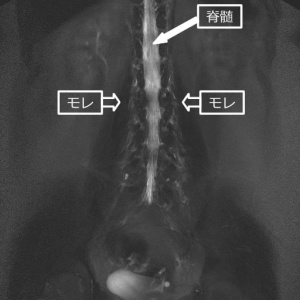

RIシンチは針で髄液内に放射性同位元素(RI:ラジオ・アイソトープ)を注入して、RIの動きや消失具合を観察する検査方法です。この際に脊髄硬膜に穴が開いていると、ちょうどしぼんだ水風船に注射器でさらに色水を加えるような状態になります。つまり、髄液内の水量が増すことによって、漏れの勢いが増します。その結果、髄液と共に放射性物質が噴水のように飛び出してくる(実際はにじみ出る)映像が撮影される事になります。

まずは、1・3・6時間後のRI映像の膀胱に検査液が写っていること。

そして、画像にもあるようにクリスマスツリー型に検査液が漏れていること。

この2つから、腰から漏れていることが判明したの。